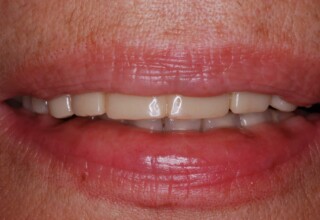

Ολική Στοματική Αποκατάσταση σε Εμφυτεύματα με διαφορετική προσέγγιση στην Άνω και Κάτω Γνάθο

Κάτω γνάθος: εξαγωγές, άμεση τοποθέτηση εμφυτευμάτων και άμεση φόρτιση(την ίδια ημέρα) με προσωρινή γέφυρα

Άνω γνάθος: σταδιακές εξαγωγές, σταδιακή τοποθέτηση εμφυτευμάτων και σταδιακή ενσωμάτωση τους στην προσωρινή γέφυρα ώστε η ασθενής να μην μείνει ούτε μια ημέρα χωρίς αποκατάσταση. Στόχος η συνεχής λειτουργική και αισθητική αποκατάσταση της ασθενούς χωρίς άμεση φόρτιση των εμφυτευμάτων λόγω ανατομικών ιδιαιτεροτήτων.

Χρησιμοποιήθηκαν παλαιές χαμογελαστές φωτογραφίες της ασθενούς γιατί είχε χαθεί τελείως το φυσικό σχήμα των δοντιών εξαιτίας των πολλαπλών προσθετικών προσπαθειών που είχαν γίνει στο παρελθόν. Μεταφέρθηκε στην προσωρινή γέφυρα η σχέση των φυσικών δοντιών μεταξύ τους άλλα και με τα χείλη. Δοκιμάστηκε η φώνηση και η μάσηση με δυο διαφορετικές προσωρινές άνω γέφυρες και εκτιμήθηκε η αισθητική απόδοση τους. Αφού επιτεύχθηκαν σε βαθμό ικανοποιητικό η φώνηση και η αισθητική εμφάνιση της οδοντοφυΐας, η προσωρινή αποκατάσταση χρησιμοποιήθηκε ως οδηγός για την τελική.